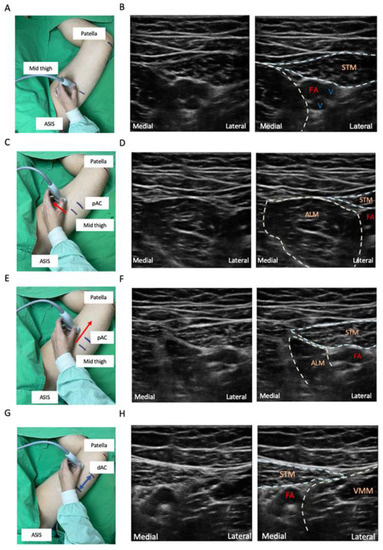

- Mark the location midway between the anterior superior iliac spine (ASIS) and the base of the patella. Place the transducer transversely on the marker of the thigh to obtain a short-axis view. The femoral vessels will be identified beneath the sartorius muscle. The artery can be distinguished by color doppler flow imaging or by compression sign (Figure 3A,B).

- Slide the probe along the medial border of the sartorius muscle to visualize the intersection of the medial borders of the sartorius muscle and the adductor longus muscle. This point means the start of the AC (Figure 3C–F).

- Slide the probe caudally until the femoral artery goes deep into the echogenic adductor magnus tendon and then passes through the adductor hiatus. This point is the end of the AC (Figure 3G,H).